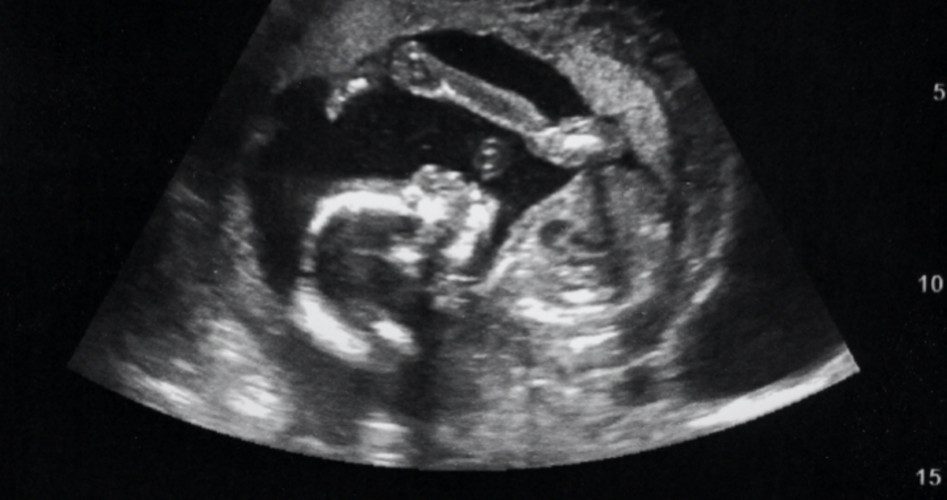

The amendment requires women to wait at least 24 hours before going through with an abortion, requires abortion facilities to give women the option of seeing their unborn babies via ultrasound and hearing their baby’s heartbeat, and requires abortion facilities to provide women with information regarding abortion risks and abortion alternatives such as adoption and parenting assistance.

And ultrasound requirements are even more effective at saving unborn lives. According to Focus on the Family, a Christian organization in Colorado Springs that provides grants to pregnancy centers for ultrasound machines, an estimated 229,500 babies have been saved since the organization implemented its ultrasound program in 2004. A 2012 study by the University of California, San Francisco, in which researchers interviewed 20 women who received an ultrasound ahead of their abortions found that there is indeed support to claims that ultrasound viewing can dissuade women from an abortion.

There’s good reason for this. Life News writes ultrasounds cut through the “evasive rhetoric” of the pro-abortion camp by showing the “reality of the unborn baby.”

Photo: strelov / iStock / Getty Images Plus